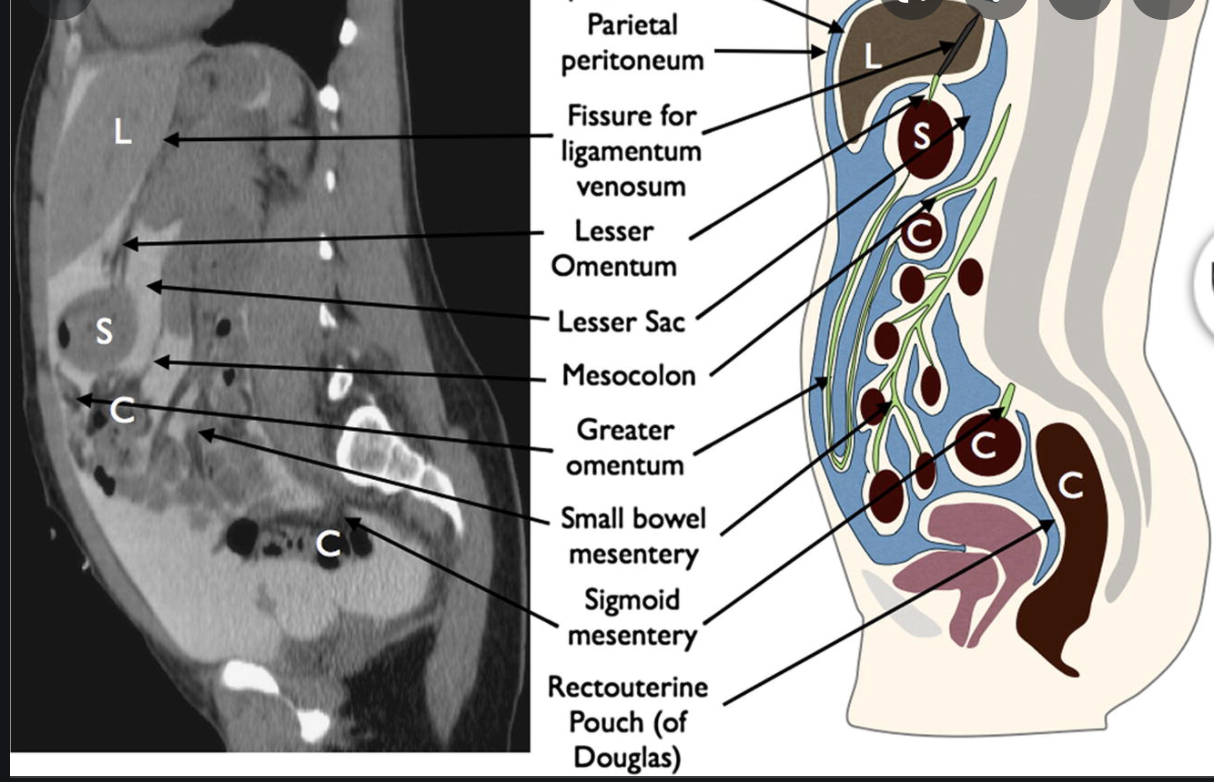

What are the Peritoneal spaces

- Subphrenic space

- divided by the falciform ligament into

- right subphrenic space between diaphragm nd liver

- left subphrenic space between diaphragm and spleen

- divided by the falciform ligament into

- Morison’s pouch

- right subhepatic recess

- hepatorenal recess

- most dependent portion of the abdominal cavity and collects fluid

- morisons pouch communicates with the

- lesser sac via the epiploic foramen

- subphrenic space

- right paracolic gutter

- Lesser Sac

- AKA Omental bursa

- posterior to the stomach and anterior to the pancreas

- medial superior extent between lesser curvature and left hepatic lobe, roofed by the gastrohepatic ligament

- access via the epiploic foramen/winslow

- Paracolic gutters

- pelvic